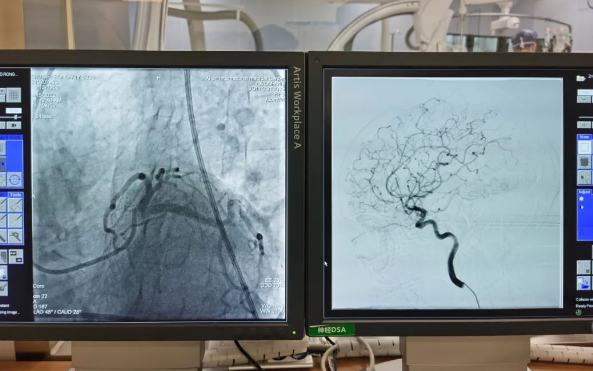

術(shù)前準備就緒后,心內(nèi)二病區(qū)曾廣偉主任、高釗副主任醫(yī)師、神外科陸丹副主任醫(yī)師共同為患者行腦血管造影術(shù) 冠狀造影術(shù)。術(shù)后,朱奶奶恢復(fù)良好。

陸丹副主任醫(yī)師介紹,由于腦血管疾病和心血管疾病有著共同的病理變化基礎(chǔ)——動脈粥樣硬化,臨床中,兩類疾病交叉存在的情況十分多見?!靶哪X同治”的模式不僅能讓患者獲得較好治療,還能夠降低患者就醫(yī)的時間成本和經(jīng)濟成本。